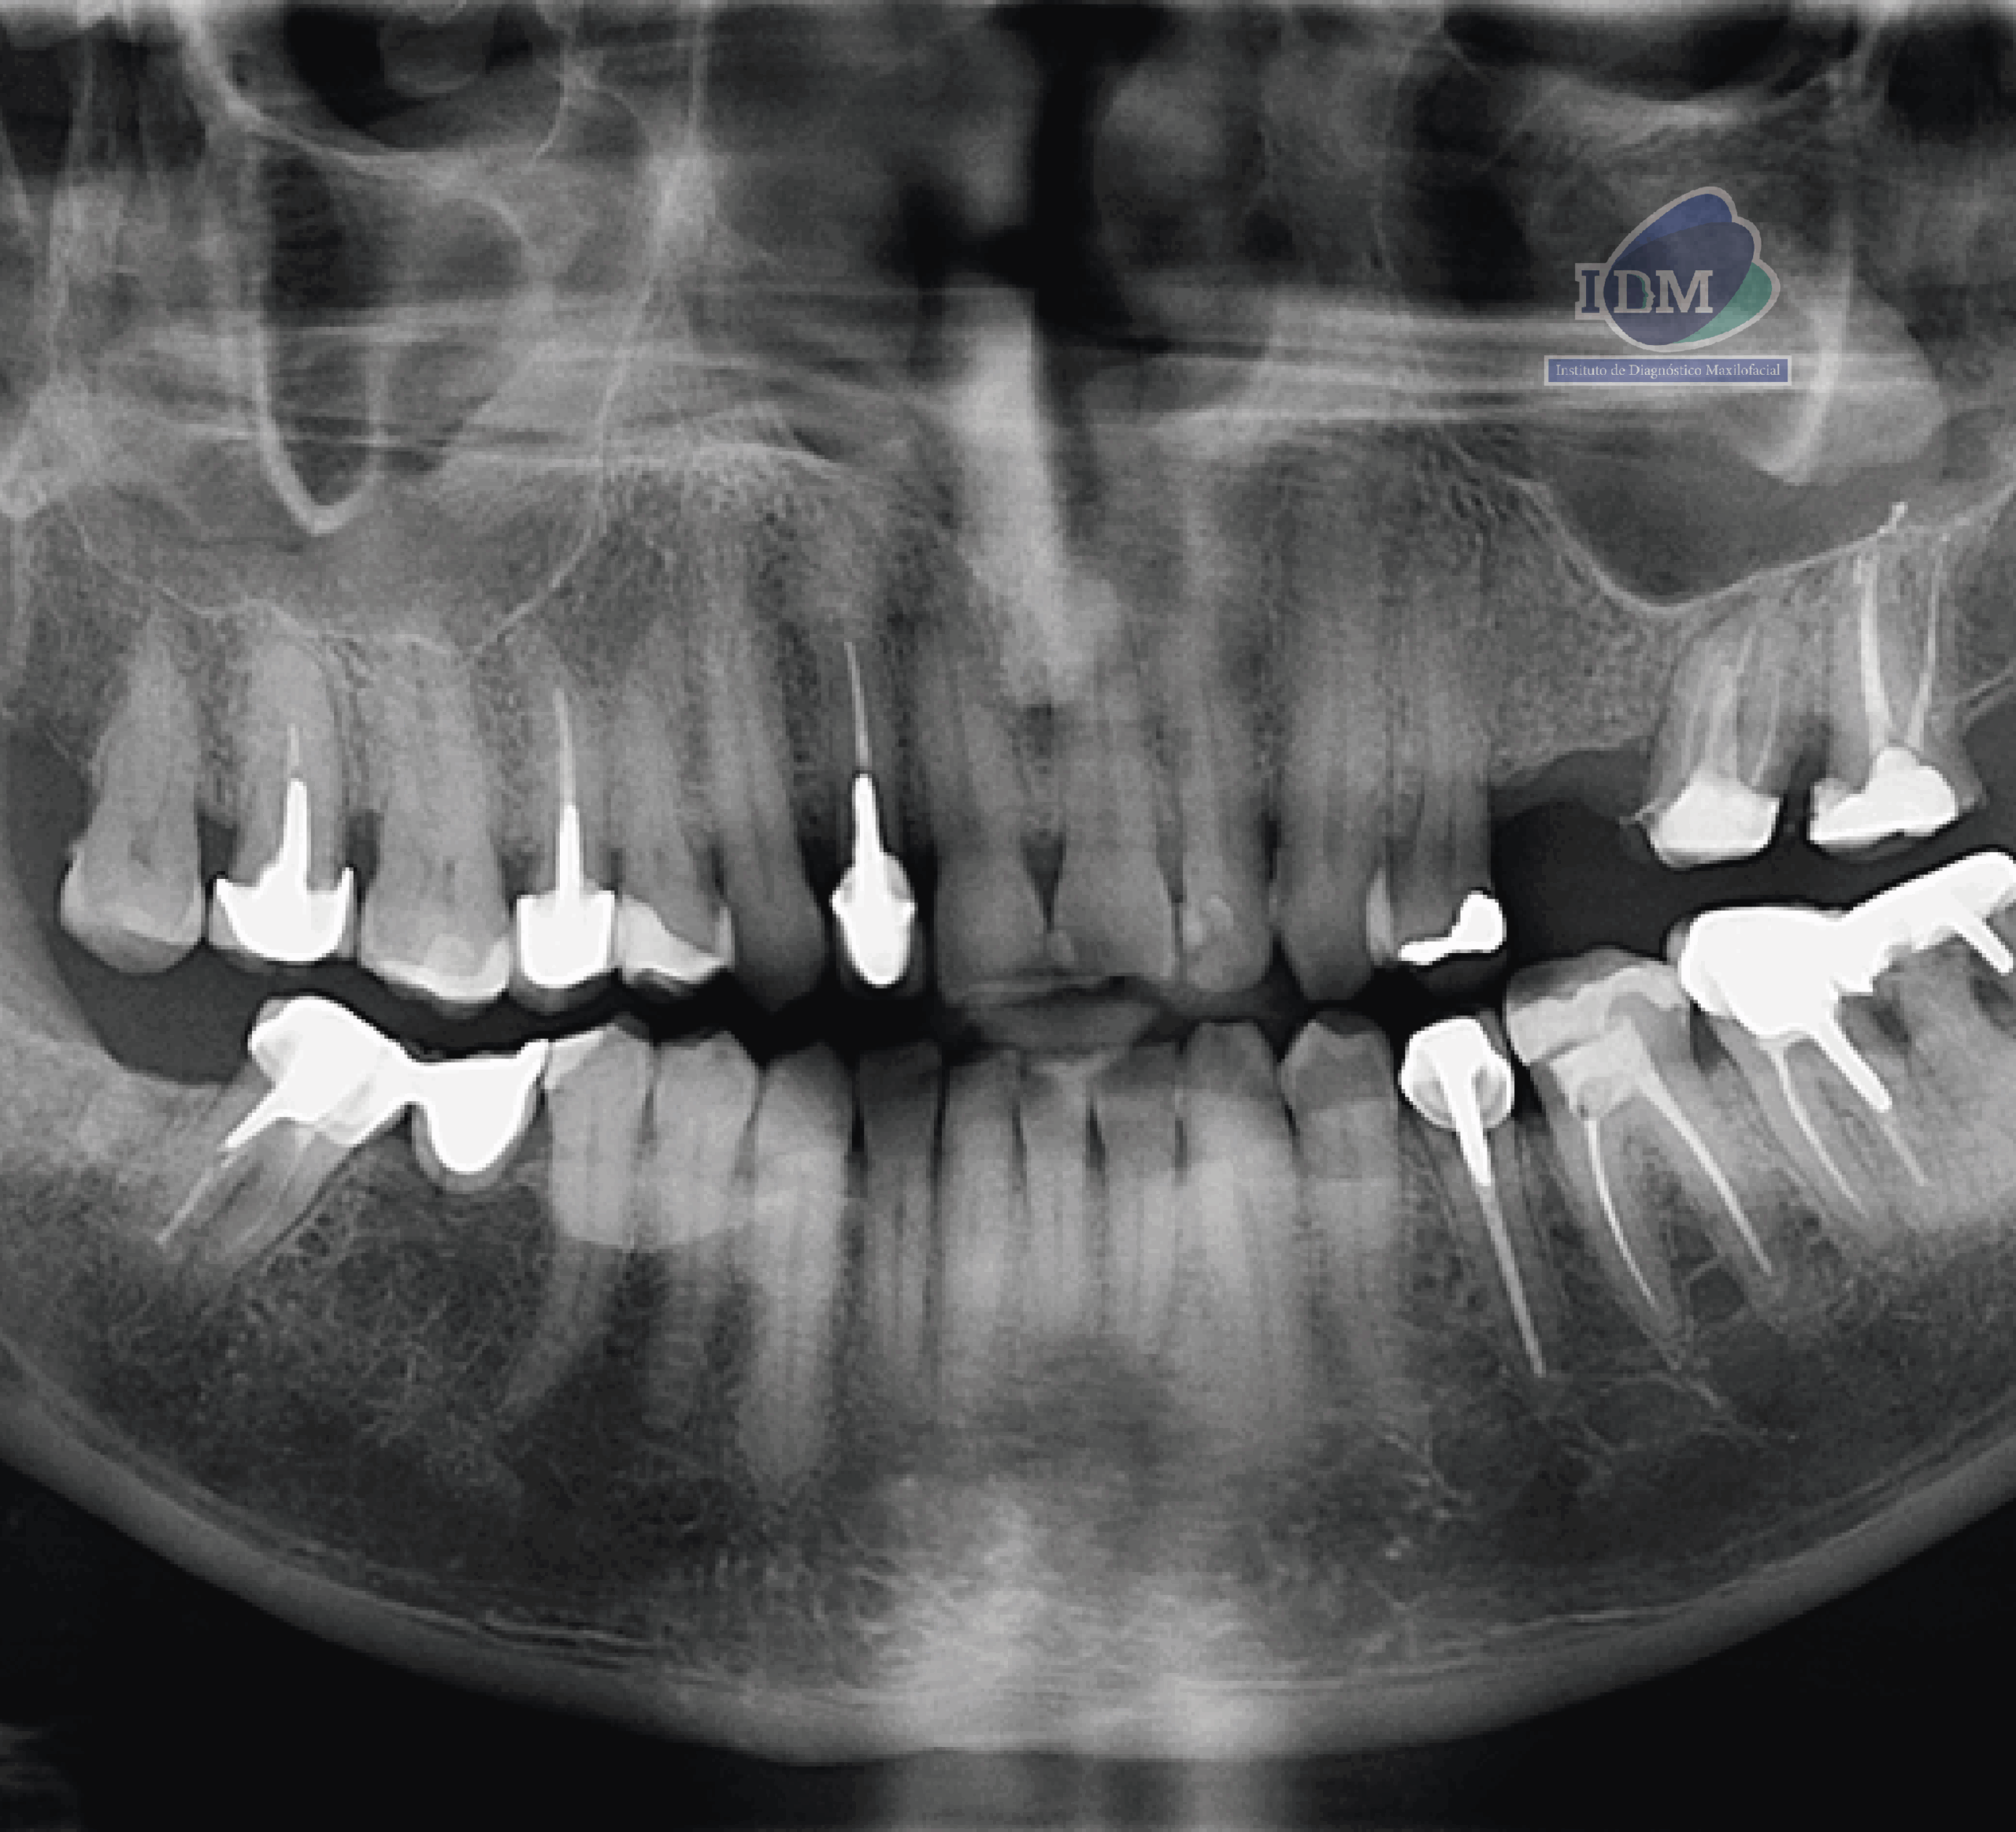

En la radiografía panorámica (Figura 1), se aprecia imagen radiopaca proyectada sobre tercio cervical y medio radicular de las piezas 36, 35, 34, 44, 45.

Radiografia Panorámica